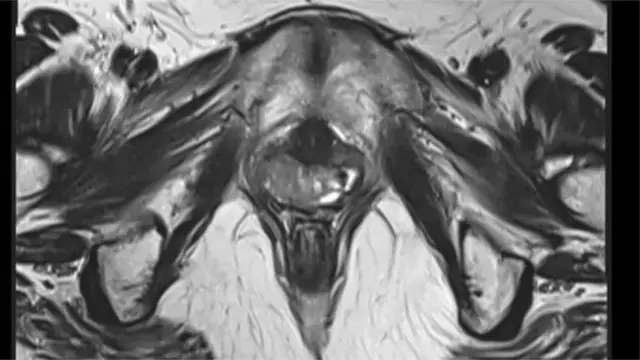

"Dhaqtarka wuxuu la yaabay xaaladdeyda xilligaas. Wuxuu i tusay sawirro muujinaya in aanan laheyn ilmo-galeenka iyo marinka xubinta taranka," ayay tiri Kesia Nascimento.

Dhaqaatiirtu waxay Nascimento u sheegeen inay marto baaritaan kale oo caafimaad. Waxay u maleynayeen in uu wax ka qaldan yahay ilmo-galeenka, markii raajada la saaray waxaa la ogaaday inay la daalaa-dhaceyso xaalad caafimaad oo naadir ah.

Markii la baaray, isla markaana la siiyay la talin caafimaad, nolosha Nascimento way isbeddeshay. Dhaqaatiirta waxay u sheegeen in gabadhan da'da yar uu ku dhacay cudur la yiraahdo Rokitansky syndrome, kaasoo sababa in dumarku ay dhashaan iyagoo aan laheyn ilmo-galeen iyo marinka xubinta taranka.